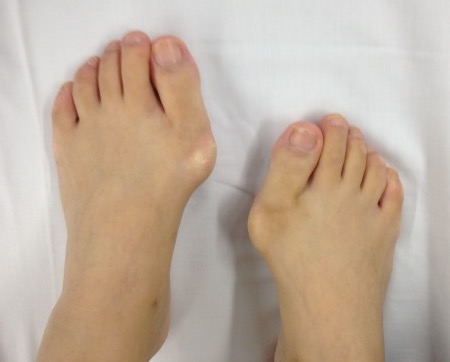

Examination

Ligamentous laxity - Beighton's score

TMTJ hypermobility

Neurological examination